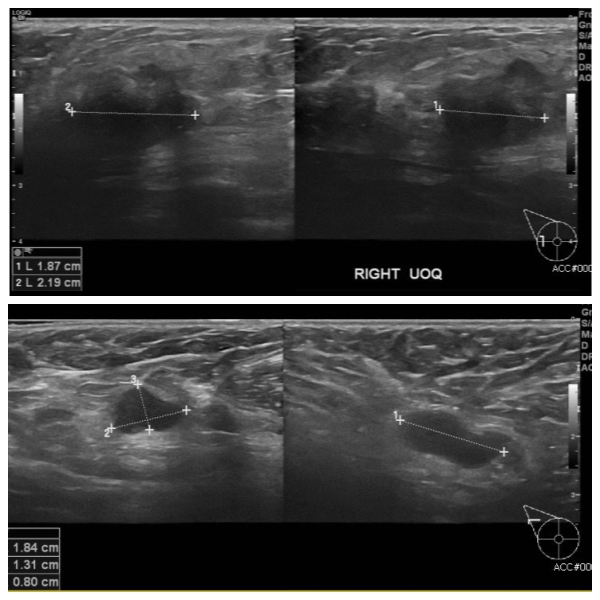

우측 유방에 만져지는 멍우리로 내원하신50대 여성분으로 우측 만져지는 멍우리 조직검사 하여 침윤성 암 진단 되었고, 겨드랑이 림프절 비대 세침검사 시행하여 전이암 진단 되었습니다.